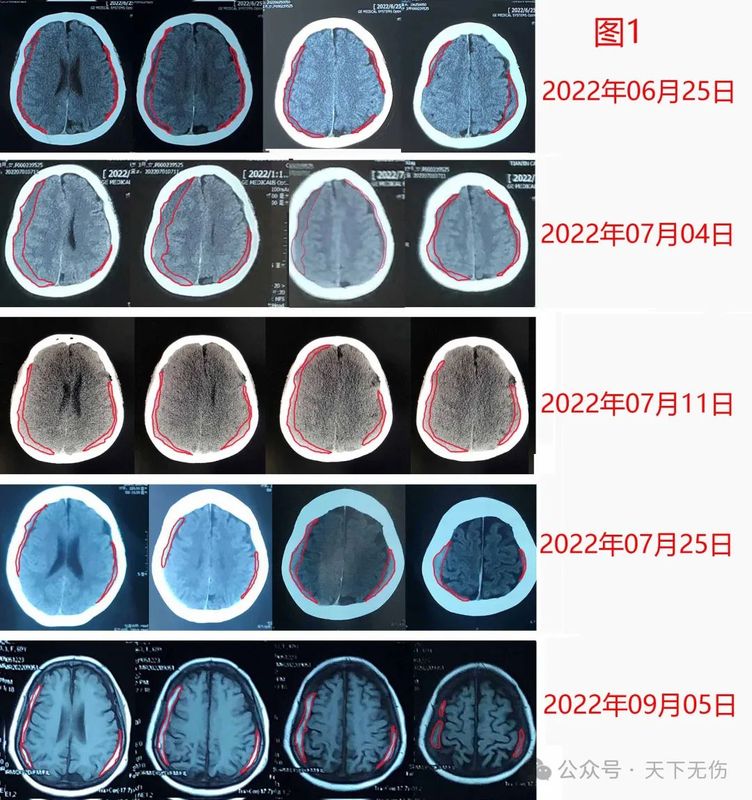

國(guó)各地求診于我的慢性硬膜下血腫患者數(shù)量在不斷增加,見(jiàn)過(guò)的患者多,各種情況就見(jiàn)得多,也因此遇到一些因應(yīng)用激素而導(dǎo)致患者疑慮、甚至自動(dòng)停藥,或者主管醫(yī)生拒絕用藥的情況;當(dāng)然更多的患者使用激素體驗(yàn)良好。L女士,69歲,是某著名醫(yī)院的著名專家,因摔傷頭部后被確診慢性硬膜下血腫。她不希望手術(shù)治療,來(lái)我門診治療。我看她的血腫量不太多,就開(kāi)具了他汀加激素治療方案。治療第1周的CT復(fù)查看到血腫沒(méi)有減少,反而略有增大。她坦白告訴我,她對(duì)激素有疑慮,沒(méi)有應(yīng)用。我為她做了解釋:我們用藥量很少,最多用4周,應(yīng)該不會(huì)對(duì)她造成永久性傷害。她聽(tīng)進(jìn)去我的解釋,開(kāi)始應(yīng)用激素,結(jié)果血腫越來(lái)越少(圖1)。2022年9月5日復(fù)查時(shí),血腫還沒(méi)有完全消失,但是她已經(jīng)正常上班。她抱怨吃激素后雙腳腫脹明顯,又覺(jué)得頭疼頭暈癥狀緩解,就自己停用了地塞米松。后來(lái)她沒(méi)有再回來(lái)復(fù)查過(guò),只是電話告知我,她已經(jīng)痊愈而且雙腳腫脹也已消除。H先生,43歲,因練習(xí)拳擊導(dǎo)致左顳部受傷后發(fā)展成慢性硬膜下血腫。他不想手術(shù),2024年10月24日輾轉(zhuǎn)從北京一家著名醫(yī)院來(lái)宣武找我門診。我給他開(kāi)具了他汀加激素藥物治療方案,叮囑他2周復(fù)查。他1周后就匆匆忙忙來(lái)復(fù)查。我看他的血腫較10月24日不僅沒(méi)有縮小,還疑似增加了,伴隨頭疼癥狀加重。問(wèn)診后才得知,他這一周主要是服用了阿托伐他汀鈣,沒(méi)有應(yīng)用激素。原因是他在口服地塞米松后不到一小時(shí),就渾身顫抖、心率加快,于是自停藥。我看他精神焦慮、頭疼明顯,就安排他住院接受手術(shù)治療。結(jié)果他非常害怕,并沒(méi)有去住院,反而是回到家中,重新?lián)炱鹞业乃〖拥厝姿煞桨福撕蟮拿看螐?fù)查,他的血腫都在減少,直到今年1月16日再次復(fù)查,確診他已經(jīng)治愈(圖2)。F先生,82歲,是某市知名糖尿病專家,他自己是糖尿病患者。他因外傷導(dǎo)致左側(cè)硬膜下血腫。老先生完全清醒,左下肢有些力弱(剛開(kāi)始我也納悶,左側(cè)血腫應(yīng)導(dǎo)致右下肢無(wú)力,為什么是左下肢無(wú)力?)。他的主管醫(yī)生征詢我意見(jiàn)后,我臨時(shí)加大了地塞米松的量。剛開(kāi)始,我還擔(dān)心老教授不愿意接受我主張的激素治療,畢竟它會(huì)干擾血糖血壓。但老教授告訴我,他搞了一輩子糖尿病,對(duì)激素的副作用完全知曉,而且自己可以調(diào)節(jié)血糖到基本正常,愿意接受我的他汀加激素治療方案。后續(xù)復(fù)查,眼見(jiàn)他的血腫逐步減少(圖3),左下肢力量也逐步增強(qiáng),我正期待他的最新復(fù)查結(jié)果。L女士,39歲,因頭部外傷導(dǎo)致左側(cè)慢性硬膜下血腫,于今年3月6日接受鉆孔引流術(shù),手術(shù)成功。她術(shù)前就有視力障礙,術(shù)后發(fā)現(xiàn)雙眼視力進(jìn)一步下降,已經(jīng)到了幾乎失眠的地步。她兩口子從外地跑到北京某著名眼科??漆t(yī)院診療,確診顱內(nèi)壓增高(400mmH2O),雙側(cè)視乳頭水腫,術(shù)后仍殘余硬膜下血腫。該眼科醫(yī)生推薦患者來(lái)找我,結(jié)果她在我診室內(nèi),就因顱內(nèi)壓增高而惡心嘔吐。我果斷收她入院,先排除顱內(nèi)靜脈竇血栓,給予激素消除視乳頭水腫,給予高滲鹽水降低顱內(nèi)壓,給予他汀消除殘余血腫。她的癥狀迅速減輕,并且告訴我,當(dāng)輸上激素時(shí),她自覺(jué)有一股清冽之氣從輸液的胳膊進(jìn)去,進(jìn)入顱內(nèi),眼睛就亮了。她是3月21日來(lái)北京那家醫(yī)院看病的,但找我看病用藥已經(jīng)是3月26日,3月29日復(fù)查CT已可見(jiàn)硬膜下血腫縮小,與癥狀消減完全符合,且僅僅治療3天(圖4)。再過(guò)2天,她的顱內(nèi)壓也降到了130mmH2O。我知道這種患者的視力恢復(fù),決定性的是正確而及時(shí)的康復(fù),她一定還會(huì)進(jìn)步。我果斷要求她出院去接受高壓氧治療聯(lián)合鼠神經(jīng)生長(zhǎng)因子注射。昨天患者出院了,她的頭痛、惡心嘔吐緩解了,視力也已部分恢復(fù)。Y老先生,96歲,是我國(guó)某醫(yī)學(xué)專業(yè)領(lǐng)域的泰斗級(jí)教授。他因?yàn)檩p微外傷發(fā)生左側(cè)硬膜下血腫,他的右手已經(jīng)不能持筷,也不能下地行走了。我建議他采用小劑量短療程激素配合阿托伐他汀鈣治療,但他有嚴(yán)重糖尿病,他的主治醫(yī)生不敢完全采納我的激素治療方案,也因此他的癥狀也就沒(méi)有緩解。我主動(dòng)聯(lián)系這位主治醫(yī)生,跟他解釋為什要用激素,他很快聽(tīng)取我的意見(jiàn),加上了小劑量激素。今天距離我會(huì)診這位前輩已是過(guò)去8天,也是他加上激素治療后的第3天。電話隨訪這位主治醫(yī)生獲悉,接受他汀加激素治療方案后,老主任的血糖一度突然升高到19mmol/L,讓所有關(guān)心主任的醫(yī)生都擔(dān)心了。這位主治醫(yī)師隨后將地塞米松改成更小劑量。今天證實(shí),老主任各方面機(jī)能、包括右手肌力已明顯緩解。我期待著一周后老主任的檢查結(jié)果給我一個(gè)驚喜。。地塞米松是1948年由美國(guó)科學(xué)家菲利普·肖瓦爾特·亨奇(PhilipShowalterHench)和愛(ài)德華·卡爾文·肯德?tīng)枺‥dwardCalvinKendall)成功從腎上腺皮質(zhì)中分離得到,并發(fā)現(xiàn)其具有顯著的抗炎作用,1950年獲得諾貝爾生理學(xué)或醫(yī)學(xué)獎(jiǎng)。1960年代,地塞米松被批準(zhǔn)用于治療多種炎癥和免疫相關(guān)疾病,地塞米松能有效減輕腦腫瘤或腦外傷引起的腦水腫,因此神經(jīng)外科常應(yīng)用它來(lái)自治療腦水腫;在腫瘤領(lǐng)域,則被用于治療化療或放療后并發(fā)癥。我國(guó)非典流行期間和COVID-19疫情中,曾廣泛應(yīng)用地塞米松治療感染患者;而英國(guó)學(xué)者報(bào)道,地塞米松可使重癥COVID-19患者的死亡率降低約1/3。地塞米松最為令人擔(dān)憂的副作用是股骨頭壞死。有統(tǒng)計(jì)認(rèn)為,長(zhǎng)期使用較大劑量的糖皮質(zhì)激素患者中,股骨頭壞死的發(fā)生率約為3%~34%。如果應(yīng)用地塞米松的劑量超過(guò)每天3mg,長(zhǎng)期使用的話,股骨頭壞死的發(fā)生率可達(dá)5%-25%。地塞米松治療慢性硬膜下血腫始于1960年代加拿大醫(yī)生的發(fā)明,而且迄今在北歐、北美還被廣泛用來(lái)預(yù)防或者治療慢性硬膜下血腫術(shù)后復(fù)發(fā)。2020年劍橋大學(xué)團(tuán)隊(duì)發(fā)表臨床研究結(jié)果認(rèn)為地塞米松相比于安慰劑沒(méi)有促進(jìn)慢性硬膜下血腫吸收,且地塞米松應(yīng)用后死亡率較對(duì)照組高,但是,劍橋團(tuán)隊(duì)在19天內(nèi)應(yīng)用地塞米松的總劑量達(dá)到了110.5mg。我認(rèn)為,激素治療慢性硬膜下血腫歷史久遠(yuǎn),且今天歐美醫(yī)生還在應(yīng)用,該方案具有生命力。雖然其副作用讓人生畏,但降低劑量則可能避免或減輕,因此,我提出了以阿托伐他汀鈣為主、以小劑量地塞米松為輔的阿托伐他汀鈣聯(lián)合地塞米松治療慢性硬膜下血腫新方案,4周的地塞米松總劑量最多是49mg,不及劍橋團(tuán)隊(duì)報(bào)道的地塞米松劑量的一半。我從2009年開(kāi)始他汀為基礎(chǔ)的藥物治療慢性硬膜下血腫研究,治療的患者數(shù)量已經(jīng)超過(guò)1400余例,而從2014年開(kāi)始的地塞米松與阿托伐他汀鈣聯(lián)合方案治療慢性硬膜下血腫患者,其數(shù)量已近千例,但僅有1例患者發(fā)生疑似發(fā)生地塞米松相關(guān)股骨頭壞死。這位患者僅接受過(guò)4周的他汀加地塞米松藥物治療,治療期間無(wú)并發(fā)癥。3年后隨訪發(fā)現(xiàn)他罹患右側(cè)股骨頭壞死,是否跟激素有關(guān)?我至今不敢確認(rèn)。我特別理解醫(yī)生和患者對(duì)地塞米松應(yīng)用的顧慮,地塞米松除了可能誘導(dǎo)股骨頭壞死,還可能擾亂血糖代謝、心率和血壓,但是,地塞米松藥物相關(guān)副作用均與劑量和療程密切相關(guān),我們的實(shí)踐證明,我們的短期、小劑量應(yīng)用方案對(duì)于絕大多數(shù)慢性硬膜下血腫患者是可靠、有效和安全的,而且多數(shù)患者加上激素療效良好。我會(huì)繼續(xù)應(yīng)用該方案治療慢性硬膜下血腫患者,但也會(huì)更加關(guān)注其安全性專家介紹江榮才教授?首都醫(yī)科大學(xué)宣武醫(yī)院神經(jīng)外科二級(jí)教授,主任醫(yī)師,博導(dǎo)?首都醫(yī)科大學(xué)宣武醫(yī)院神經(jīng)外科神經(jīng)外科副主任兼任危重癥中心主任?中華醫(yī)學(xué)會(huì)神經(jīng)外科學(xué)分會(huì)委員、腦外傷學(xué)組副組長(zhǎng)?中國(guó)醫(yī)師協(xié)會(huì)神經(jīng)外科醫(yī)師協(xié)會(huì)神經(jīng)重癥專委會(huì)副主任委員?國(guó)家創(chuàng)傷醫(yī)學(xué)中心顱腦創(chuàng)傷專業(yè)委員會(huì)副主任委員?中國(guó)老年保健協(xié)會(huì)神經(jīng)外科學(xué)創(chuàng)新與轉(zhuǎn)化分會(huì)首任會(huì)長(zhǎng)?擅長(zhǎng)復(fù)雜重型腦外傷、腦出血及慢性硬膜下血腫的診療。?是他汀治療硬膜下血腫的主要發(fā)明者,治療慢性硬膜下血腫患者超1400名,總治愈率約90%?!境鲈\時(shí)間】每周四下午(神經(jīng)外科專家門診)每周三上午(神經(jīng)外科特需門診)